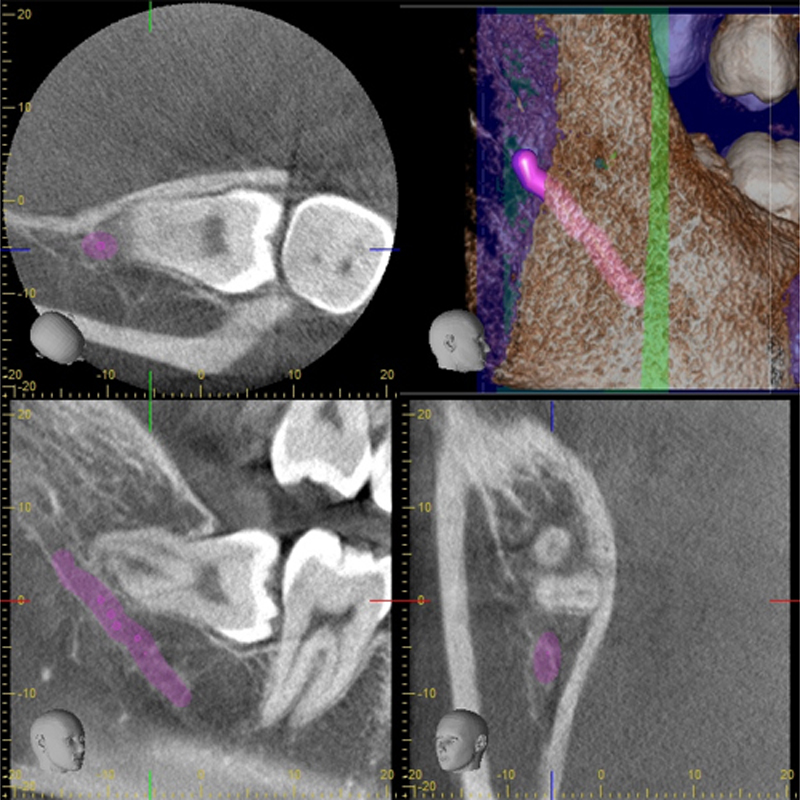

親知らずが横を向いて埋まっていて隣の歯が虫歯になったり、清掃性が悪いために炎症を起こして腫れてしまうリスクが高いために抜歯をしたほうがいいケースです。親知らずと神経が近い場合は安全のためにCT撮影をして位置関係を確認します。

顎の神経と埋もれている親知らずの根の先の近接を認めるため、

主訴:右下に違和感があり、以前右上の親知らずにも痛みがあった。

右下の親知らずの根の先は顎の神経根に近接を認めるため、